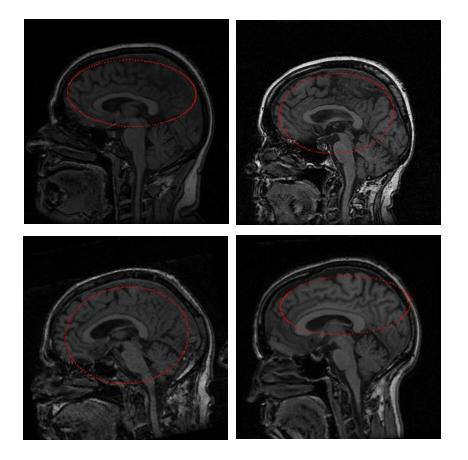

The ellipsoid obtained is reduced in scale by approximately half. The initial ellipsoids in all the test images evolved to reasonable brain surface approximations in a reasonable amount of time. Figure 1 shows the ellipsoid of intersection of the ellipsoid with the middle slice of the images.

Figure 1. The initial ellipsoids intersected with the middle slices.